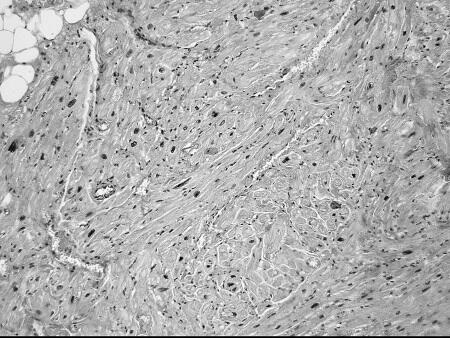

Что же общего среди всех этих состояний и что определяет их патогенетическую взаимосвязь с ФП? Очевиден механизм нарушения электрических процессов в результате ремоделирования миокарда. Данные патологоанатомических исследований подтверждают это. Так, при гистологическом исследовании ткани предсердий умерших пациентов с ФП часто выявлялись следующие изменения (см. рис. 5):

дистрофические изменения кардиомиоцитов, гипертрофия кардиомиоцитов (см. рис. 5 а б);

а)

б)

Рисунок 5.Гистологические изменения предсердий при ФП